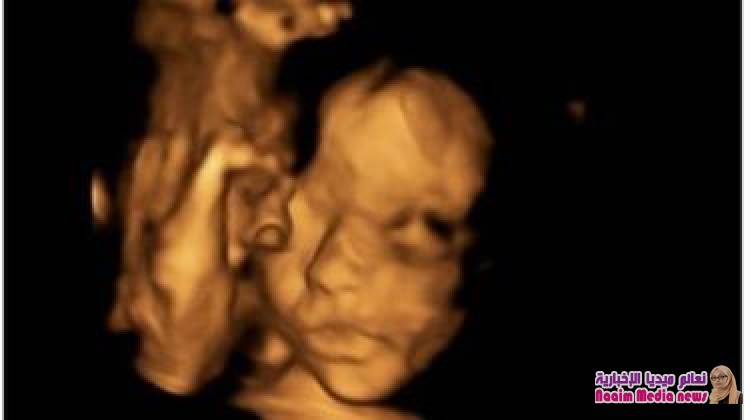

أجرى أطباء بريطانيون عملية في العمود الفقري لجنين بينما كان لا يزال في رحم أمه.

وقد فتح الرحم خلال العملية التي استمرت 4 ساعات، وتمكن الأطباء من إجراء رتق في الجزء الخلفي من العمود الفقري.

وفتح الرحم خلال العملية الجراحية التي أجريت في الأسبوع الرابع والعشرين من الحمل ورفع الجنين في وضع يسمح بالوصول إلى عموده الفقري وإجراء الجراحة ومن ثم إعادة الحبل الشوكي إلى مكانه.